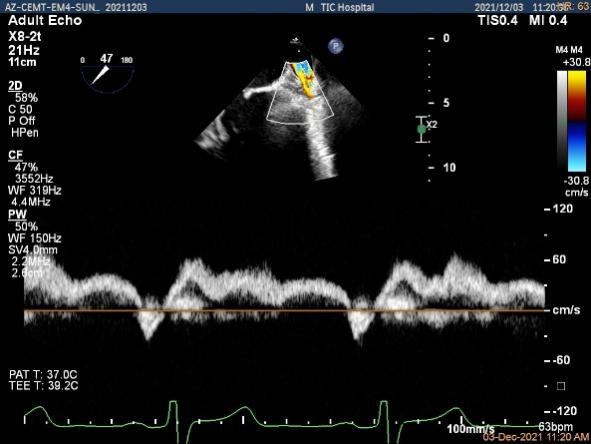

肺静脉血流频谱恢复正向